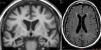

Dementia is a syndrome characterised by chronic, multi-domain, acquired cognitive impairment that causes significant functional limitations. MRI is the standard imaging study for these cases, since it enables detection of the atrophy patterns of the various neurodegenerative diseases (Alzheimer's disease, frontotemporal degeneration, Lewy body dementia), the vascular lesions associated with vascular dementia, and various potentially reversible diseases (for example, tumours, hydrocephaly) or diseases that require special management measures (for example, prion diseases). In certain cases other imaging methods can be used, such as CT, functional MRI, HMPAO SPECT or dopaminergic markers and FDG PET, amyloid markers or dopaminergic markers. The indications for these methods have not yet been clearly established, and therefore should be used in multidisciplinary dementia units.